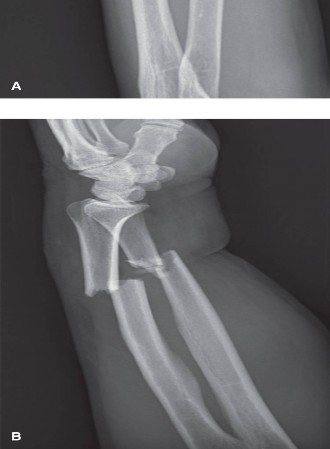

Standard orthogonal imaging, including true anteroposterior (AP) and lateral radiographs of the forearm, elbow, and wrist, is mandatory. The integrity of the PRUJ and DRUJ must be critically assessed to rule out associated Monteggia or Galeazzi fracture-dislocations.

Contralateral templating is a cornerstone of preoperative planning. Radiographs of the uninjured forearm provide an individualized template of the patient's native radial bow magnitude and location. In complex comminuted fractures or established malunions, computed tomography (CT) with three-dimensional reconstructions is highly recommended. Advanced planning software can mirror the contralateral intact radius, allowing for precise calculation of the required osteotomy angles or the degree of plate contouring necessary to restore the native anatomy.